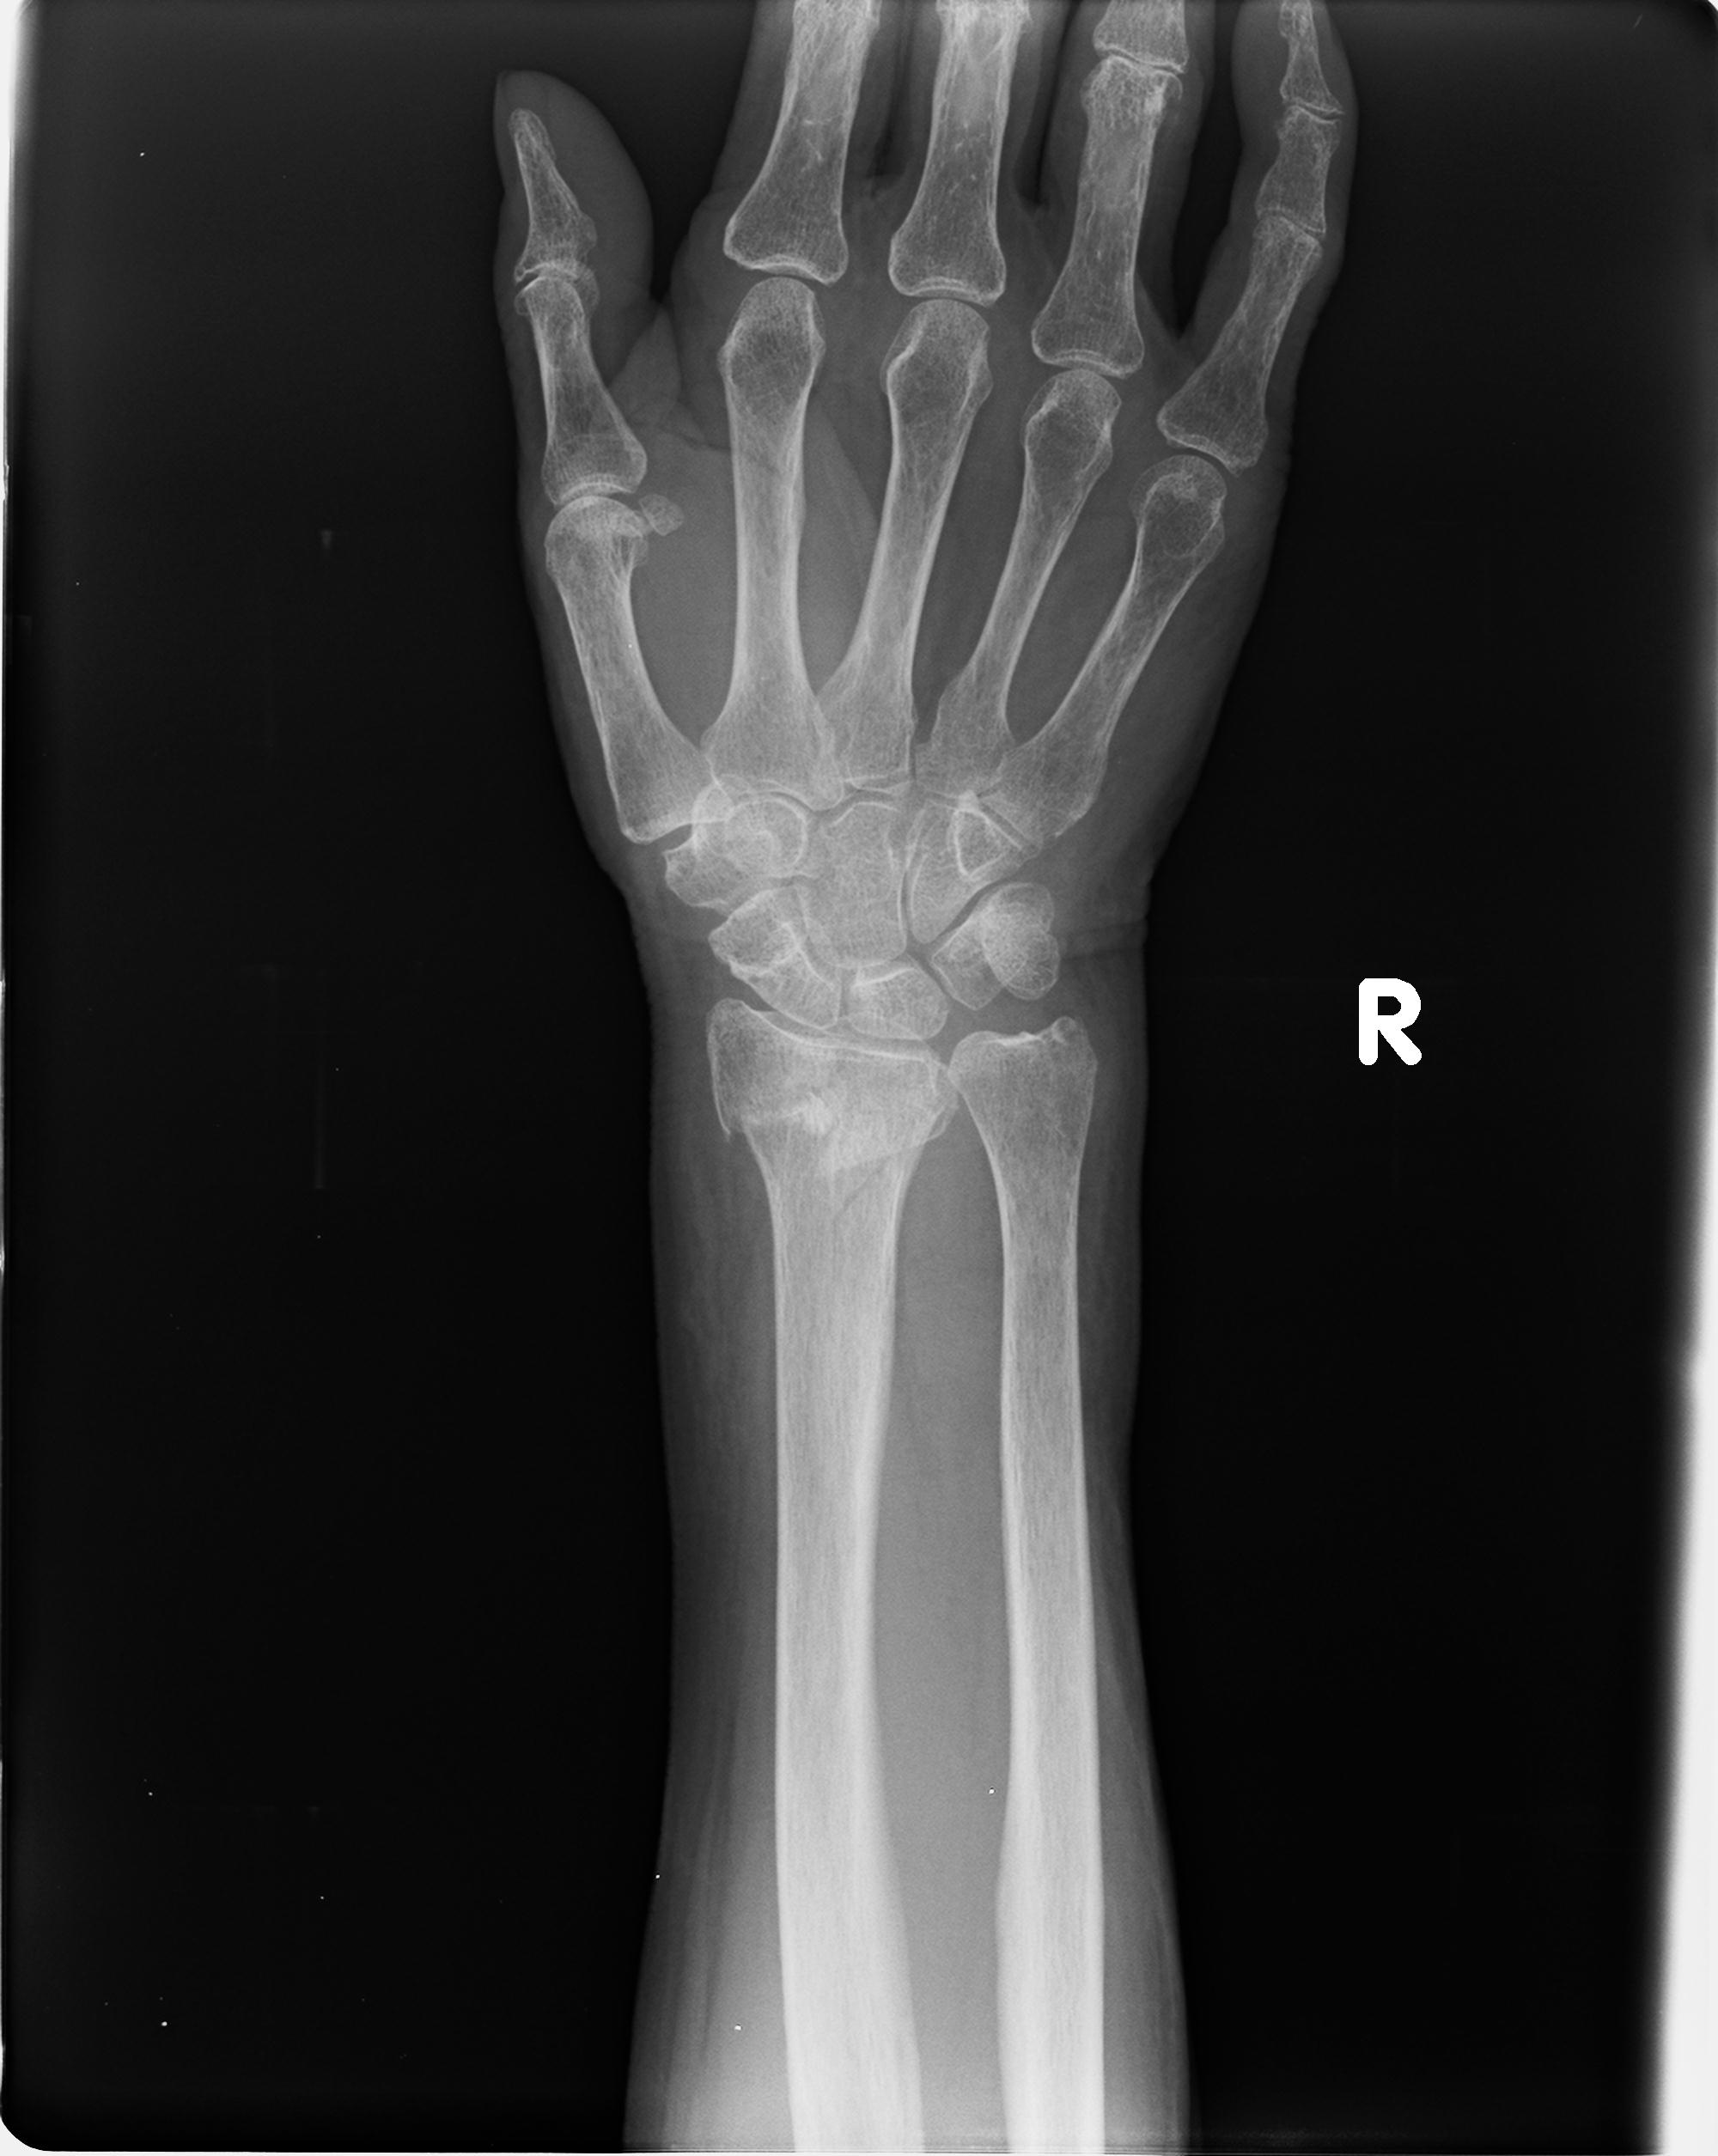

50435 1/4 1/15 手関節 4R 17歳女性 右橈骨遠位端

101290 1/4 5/21 5/20 手関節 2R 17歳男性 橈骨遠位端